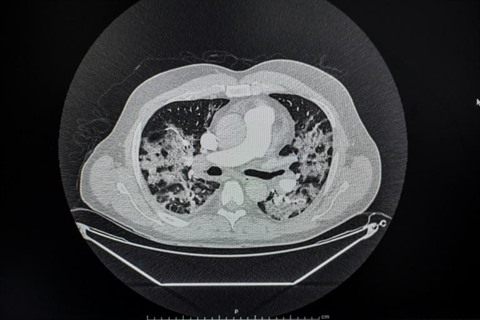

| Image des poumons d'un patient atteint de COVID-19 en soins intensifs à l'Hôpital franco-britannique de Levallois-Perret, le 9 avril. |

| Photo : AFP/VNA/CVN |